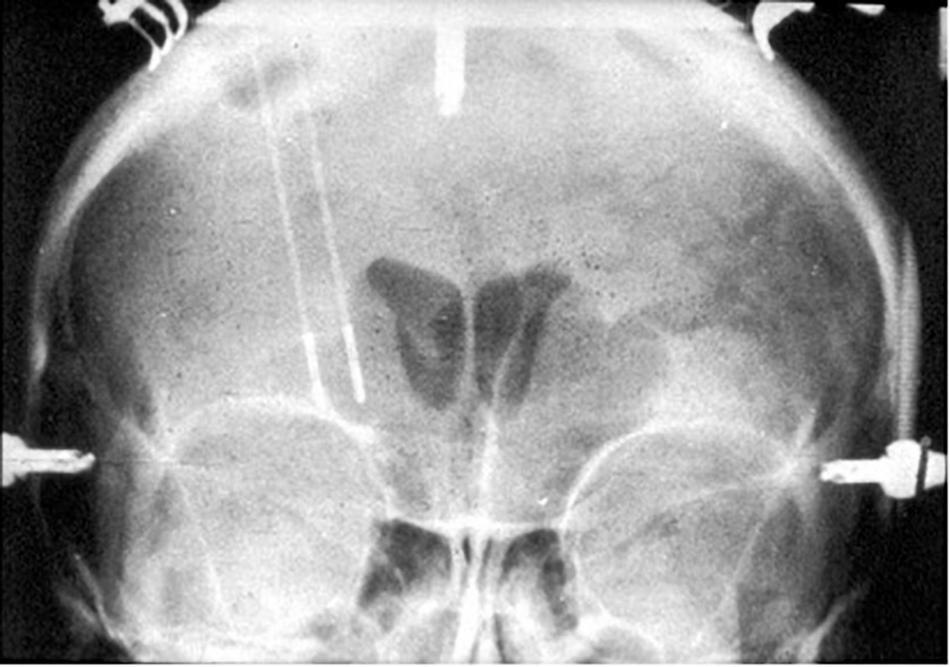

FIGURE 2

Coronal X-ray of electrodes in place for creation of Leksell’s right frontal capsulotomy lesions.